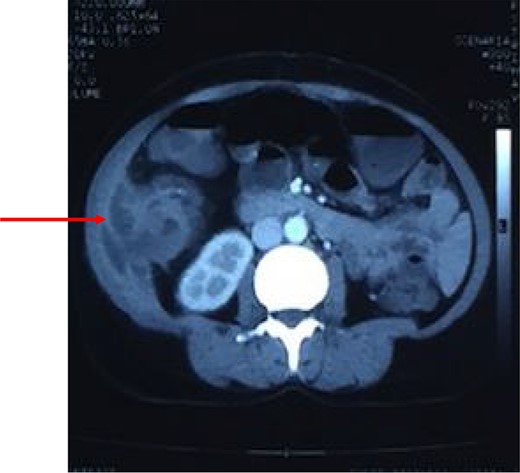

Coronal reconstruction of CT shows mass extending from colon and invading into anterior abdominal wall. Arrows indicate the point of exit of mass through the abdominal wall musculature.

After resuscitation with intravenous fluids, administration of broad-spectrum intravenous antibiotics and intravenous analgesics, a contrast-enhanced computed tomography (CECT) scan was done to further characterize the lesion. CECT of abdomen showed large abscess extending from the subcutaneous and intermuscular planes over the right iliac fossa and breaching the peritoneum. It showed heterogeneous wall thickening of the proximal part of the ascending colon with loss of mural stratification and causing luminal narrowing, measuring 4.8 × 5.1 × 4.5 cm with surrounding inflammatory changes with adjacent well-defined collection 11.3 × 4.5 × 10.9 cm and few air pockets and infiltrating the right lower abdominal wall (Fig. 2). Pus aspirated from the right abdominal swelling and was sent for culture and sensitivity. Patient was taken up for diagnostic laparoscopy and proceeded.